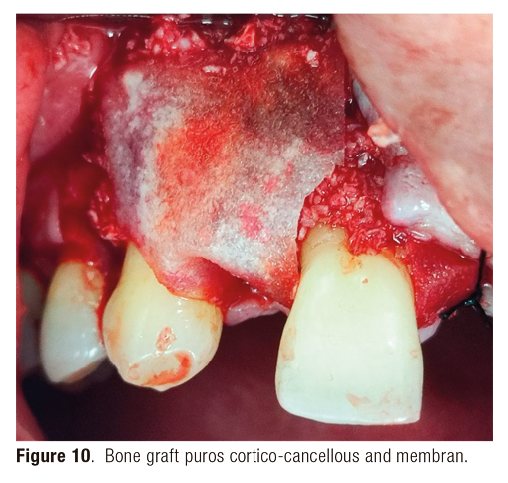

A male patient in sixth decade of life who presented a type III socket with a dehiscence <75% with thin biotype by this reason it is decided to bone regeneration with puros, cortico-cancellous bone and membrane (Figure 10).